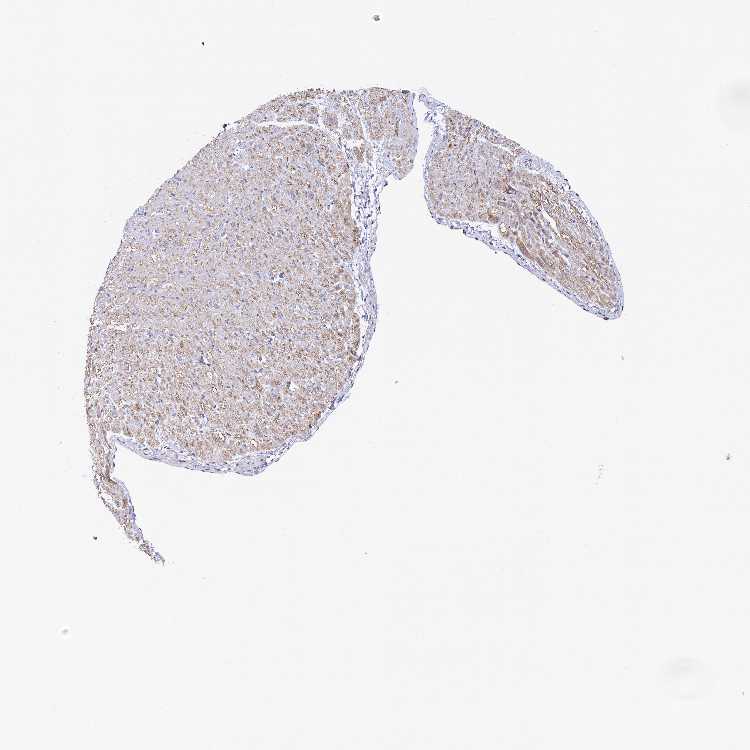

HEART MUSCLE - Antibody stainingi

Antibody staining in the annotated cell types in the current human tissue is reported as not detected, low, medium, or high, based on conventional immunohistochemistry profiling in selected tissues. This score is based on the combination of the staining intensity and fraction of stained cells.

Each image is clickable and will lead to virtual microscopy that enables deeper exploration of all samples and also displays staining intensity scores, fraction scores and subcellular localization as well as patient and tissue information for each sample.

Antibody HPA040719

Cardiomyocytes Medium